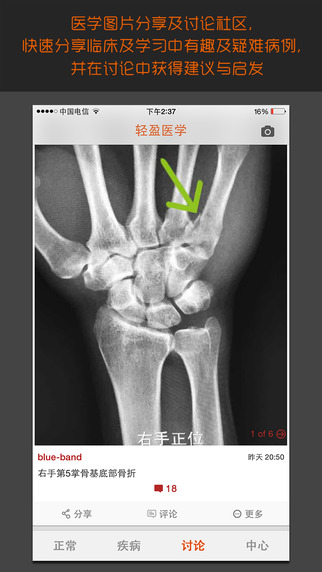

轻盈医学建立了专业的医学图片分享与交流社区,让您可以与全国各地的医学同行实时互动。在社区中,您可以分享疑难病例、讨论诊断思路、请教专家意见,还能参与各类专业话题的讨论。我们设置了严格的用户认证机制,确保社区的专业性和安全性。无论是临床困惑还是学术探讨,这里都能找到志同道合的伙伴和权威专业的解答。